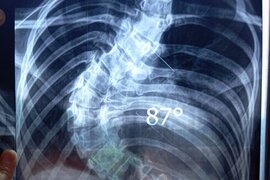

Səkinənin sizin köməyinizə ehtiyacı var

2005 təvəllüdlü İsgəndərova Səkinə Sakit qızının sizin köməyinizə ehtiyacı var. O, anadan gəlmə ağır dərəcəli skolioz, onurğanın deformasiyası, kifoz əyilmə nəticəsində ağciyəri deformasiya olub.Hal-hazırda ciddi müalicə üçün qısa zamanda yardıma ehtiyacı var. Həkimlər onun təcili əməliyyat edilməl